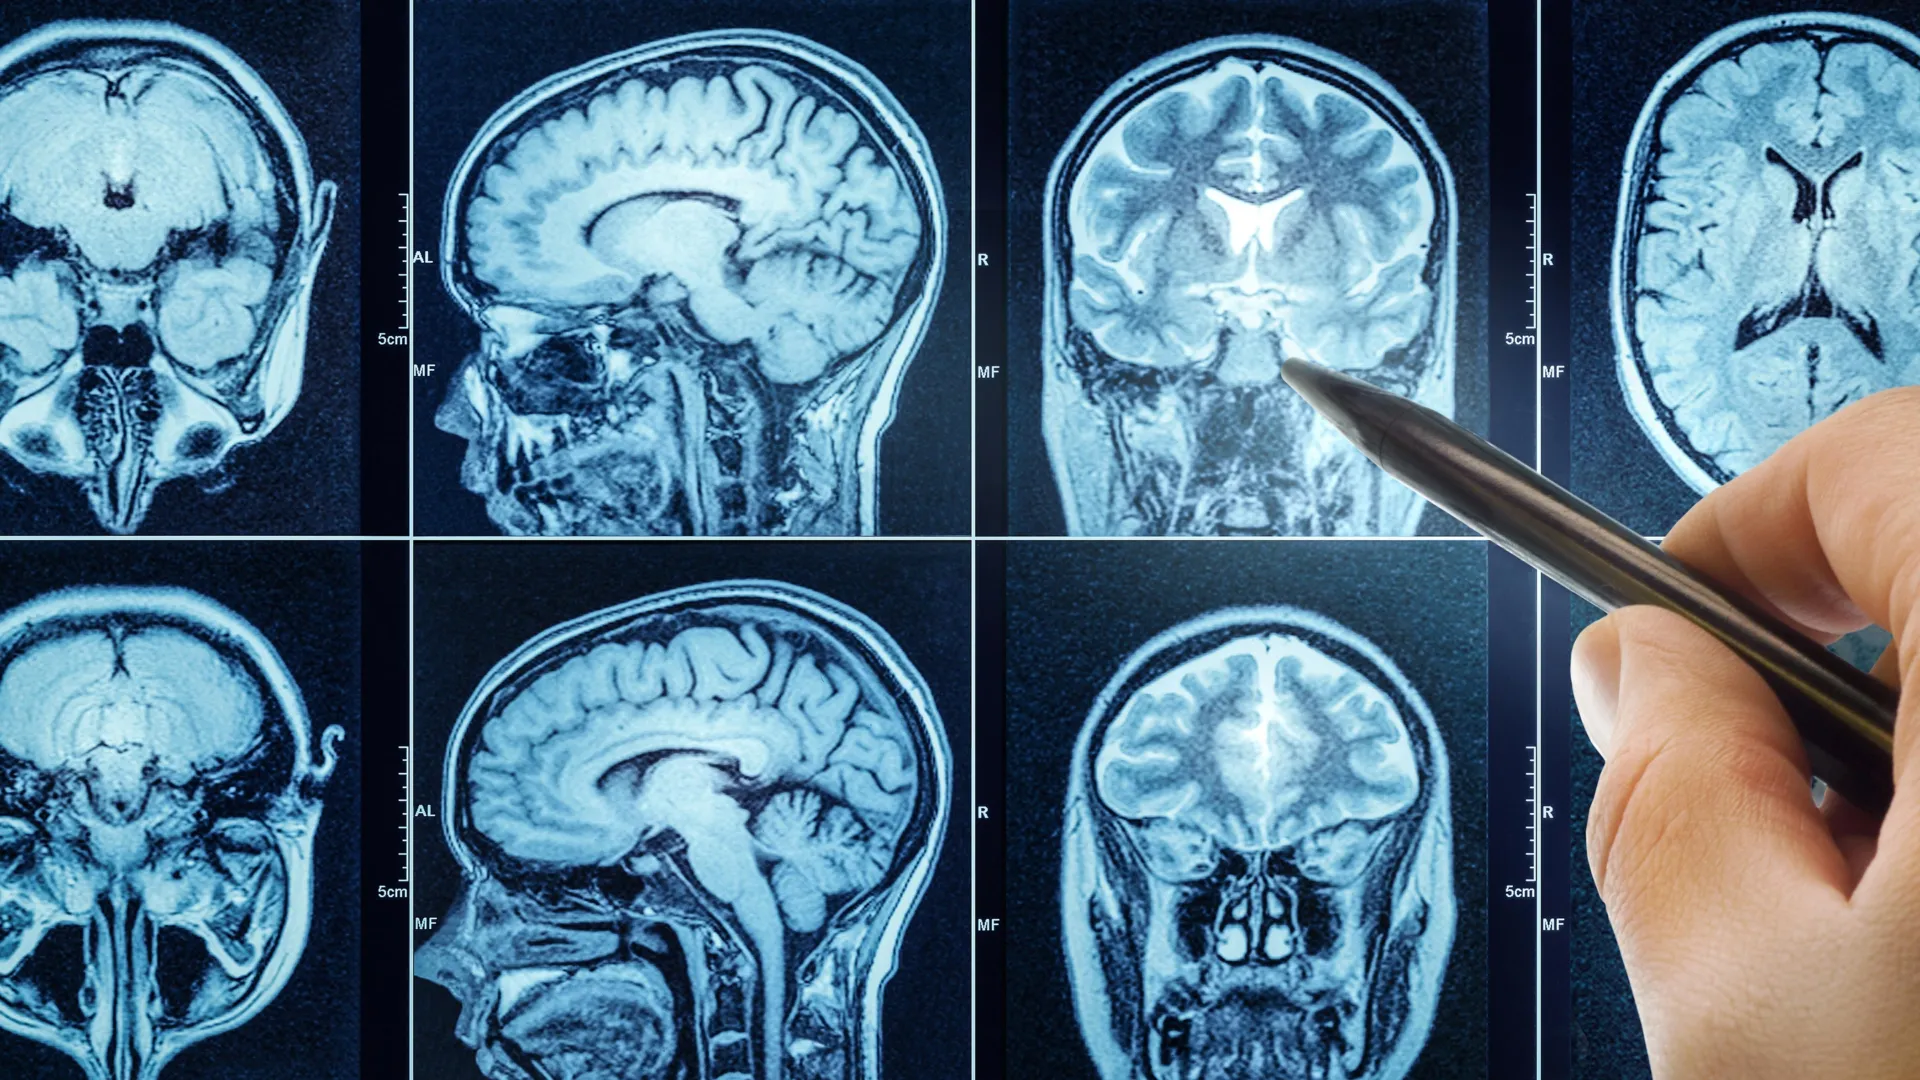

People who sleep poorly are more likely than others to have brains that appear older than they actually are. This is according to a comprehensive brain imaging study from Karolinska Institutet, published in the journal eBioMedicine. Increased inflammation in the body may partly explain the…